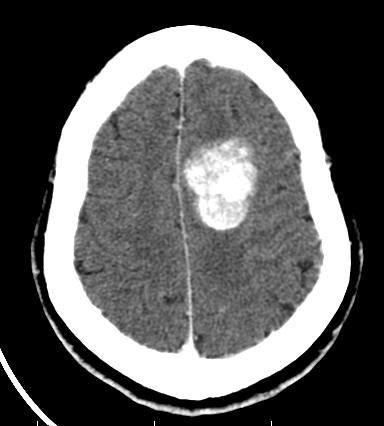

患者头痛头晕,门诊就诊。

脑膜瘤钙化,可以定期复查

钙化型脑膜瘤

就是脑膜瘤,位置表浅,钙化明显,外形光滑。